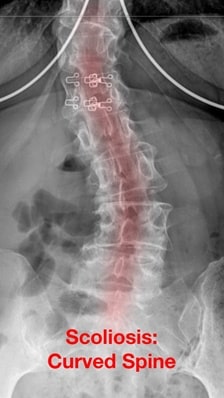

As the disc degenerates, many things can happen. As the disc collapses it can put undue stresses on the facet joints and cause the formation of bone spurs and reactive tissue that can compress the nerves. The disc can also break into pieces which can migrate into an area that puts pressures on nerves (herniated / bulging disc). In addition, disc degeneration can lead to excessive motion in the spine (spondylolisthesis) and abnormal curvature of the spine (scoliosis). In all, these different processes can results in nerve compression which can manifest as many different symptoms including numbness, tingling, burning, weakness, muscle cramps, radiating pain (in arms, legs), neck / midback / lower back pain, balance issues and bowel and bladder problems.